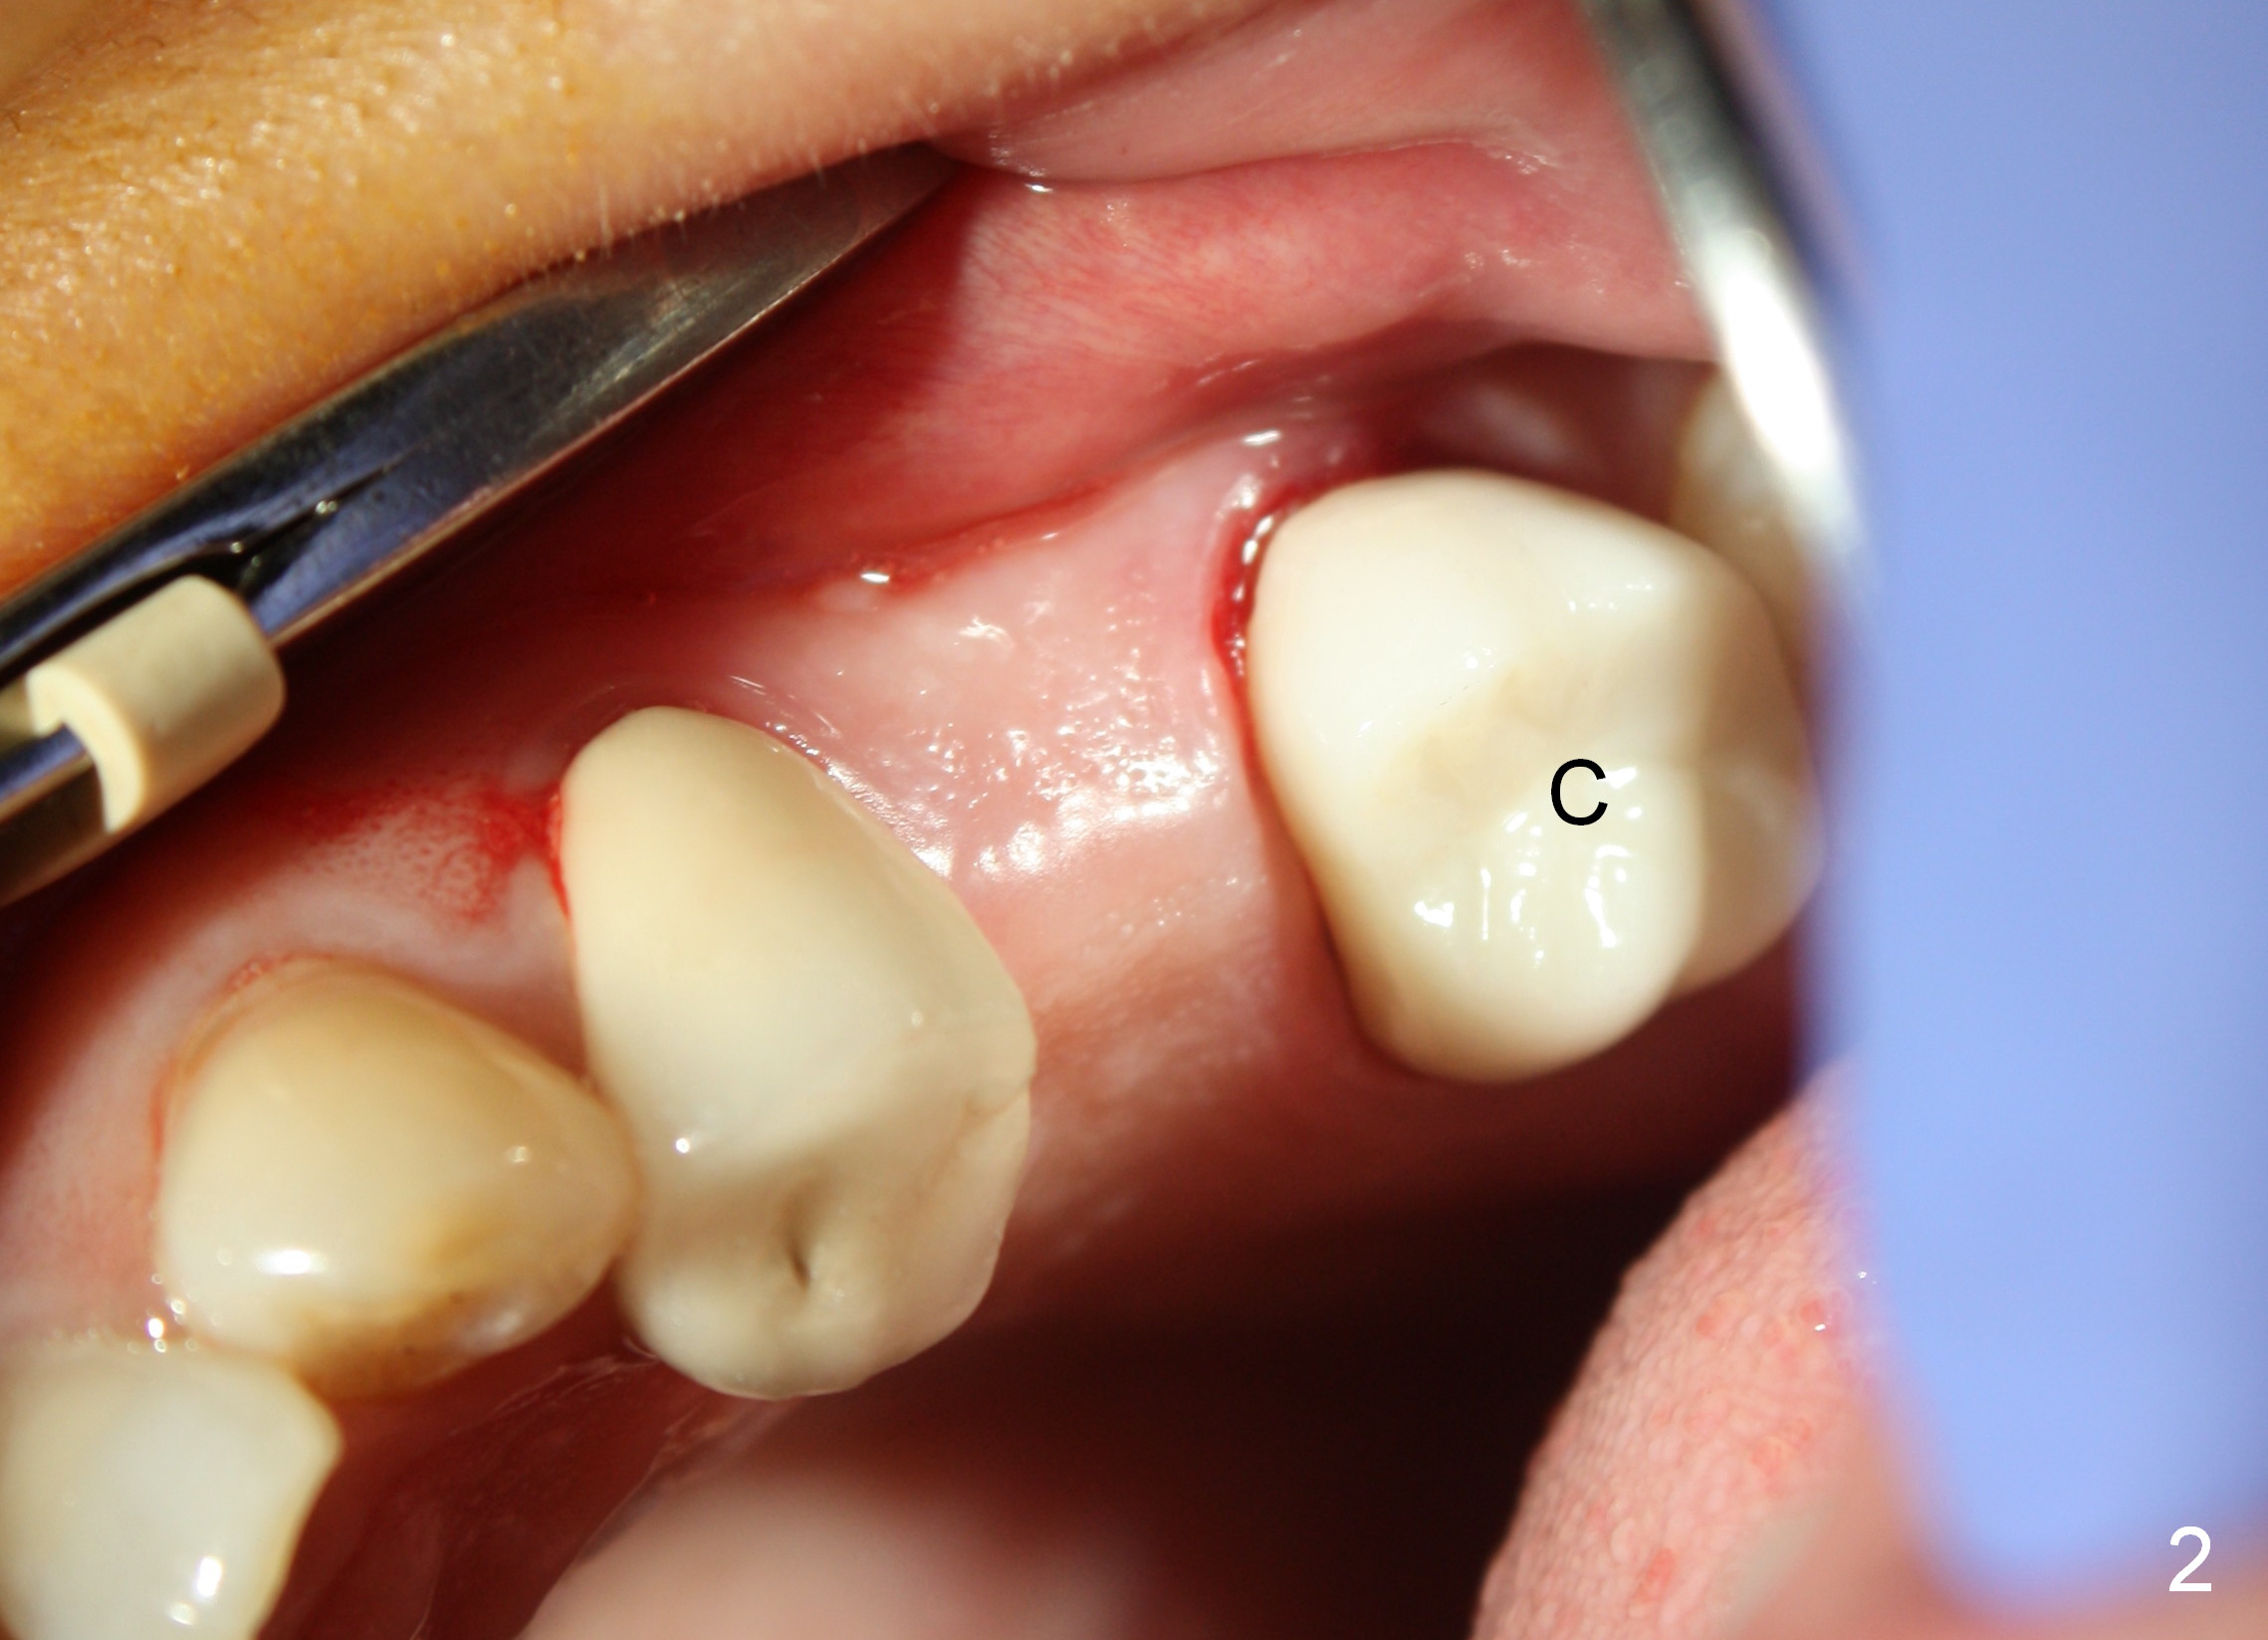

A 45-year-old lady is nervous about dental treatment. The missing tooth #13 was replaced by a 3-unit bridge. The latter is sectioned because the posterior abutment has caries. PA in Fig.1 is taken when root canal therapy and build up are finished. Fig.2 shows the wide edentulous area with a single-unit crown being tried in for #14. Osteotomy is initiated with the crown in place without cementation, since it is easy to determine the mesiodistal position (Fig.3 red lines). Without the crown in place, osteotomy tends to be distal. In this case, the osteotomy is later attempted to be moved distally with Lindamann bur and deepened to 14 mm from the gingival margin (Fig.4). A 2.5 mm reamer is being used at 50 RPM to increase osteotomy with difficulty. Drills have to used at high RPM instead (Fig.5 4x14 mm). A 4.5x14 mm tissue-level implant is placed with insertion torque >60 Ncm (Fig.6 I); a 4x3 mm abutment (A) is placed immediately for an immediate provisional. Fig.7 is taken 7 days postop to show the gingival recipient site formed by the provisional. The patient is so afraid of X-ray that the next one is taken 1.5 years post cementation (Fig.8). It appears that dense bone bundle forms between the crest and the 1st implant thread (adaptation functional change, arrowheads). The bone density continues to increase 2 years 8 months post cementation (Fig.9 *, 10); the bone has grown into the area between the 1st 2 threads (arrow).